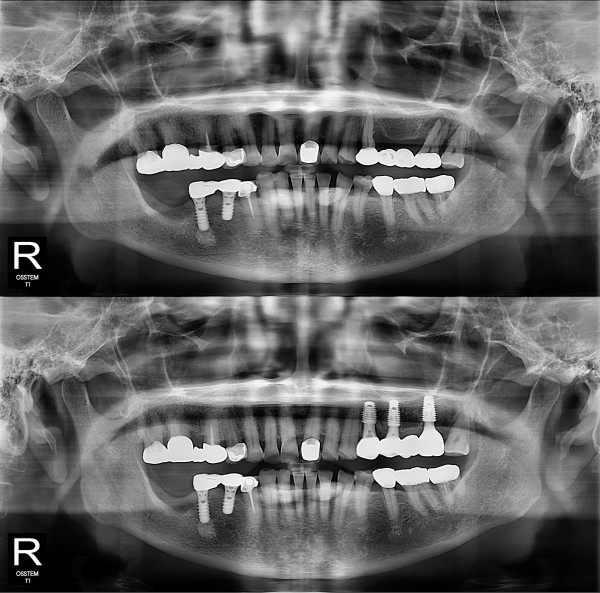

임플란트

부분 임플란트